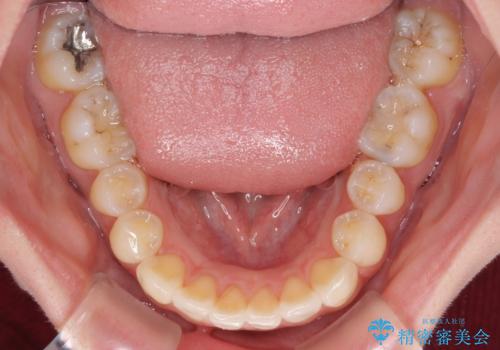

- 前歯のクロスバイトや残存している乳歯を気にして来院された患者様です。

上顎骨の幅が下顎骨よりも小さいので、拡大装置により骨幅を広げて上下関係を改善し、その後インビザラインにて歯並びを整えることとしました。

上下の骨幅を改善したことで、スムーズに歯列矯正を行うことができました。